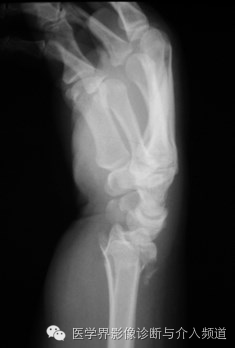

8、Barton’s骨折

桡骨远端骨折。骨折线累及桡腕关节面及桡骨远端背侧缘,为关节囊内骨折。受伤机制摔倒时候手撑地呈过伸状。

9、反Barton’s骨折

桡骨远端骨折。骨折累及桡腕关节面及桡骨掌侧缘,而Barton’s骨折累及的是桡骨背侧缘,为关节囊内骨折。受伤机制摔倒时候手撑地呈过屈状。